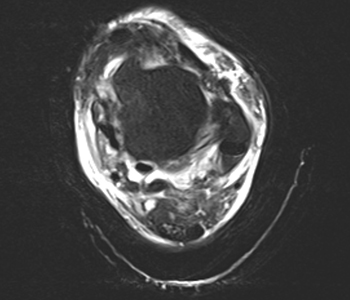

°áÀýÁ¾ ¼ö¼ú

ÀÏÁ¤±â°£ ºñ¼ö¼úÀû Ä¡·á¿¡µµ ºÒ±¸ÇÏ°í ¸¸¼ºÀû ÅëÁõÀÌ Áö¼ÓµÉ °æ¿ì ¼ö¼úÀ» °í·ÁÇÒ ¼ö ÀÖ½À´Ï´Ù.

ÃÊÀ½ÆÄ À̹ÌÁö

°áÀýÁ¾ Á¦°Å¼ú

ÈäÅͰ¡ ÀûÀ½

ÀÏ»ó»ýȰ ºü¸¥ º¹±Í

¼ö¼ú ¹× ½Ã¼ú ÈÄ ±¹¼Ò°¨¿°, ºÎºÐÃâÇ÷ ¹× ÀϽÃÀû ½Å°æ¸¶ºñ¿Í °°Àº ºÎÀÛ¿ëÀÌ µå¹°°Ô ¹ß»ýÇÒ ¼ö ÀÖ¾î º» ¼ö¼ú ¹× ½Ã¼ú ½ÃÇà ½Ã »çÀü°Ë»ç ¹× ÁÖÄ¡ÀÇ¿ÍÀÇ Àü¹® »ó´ãÀÌ ÇÊ¿äÇÕ´Ï´Ù.